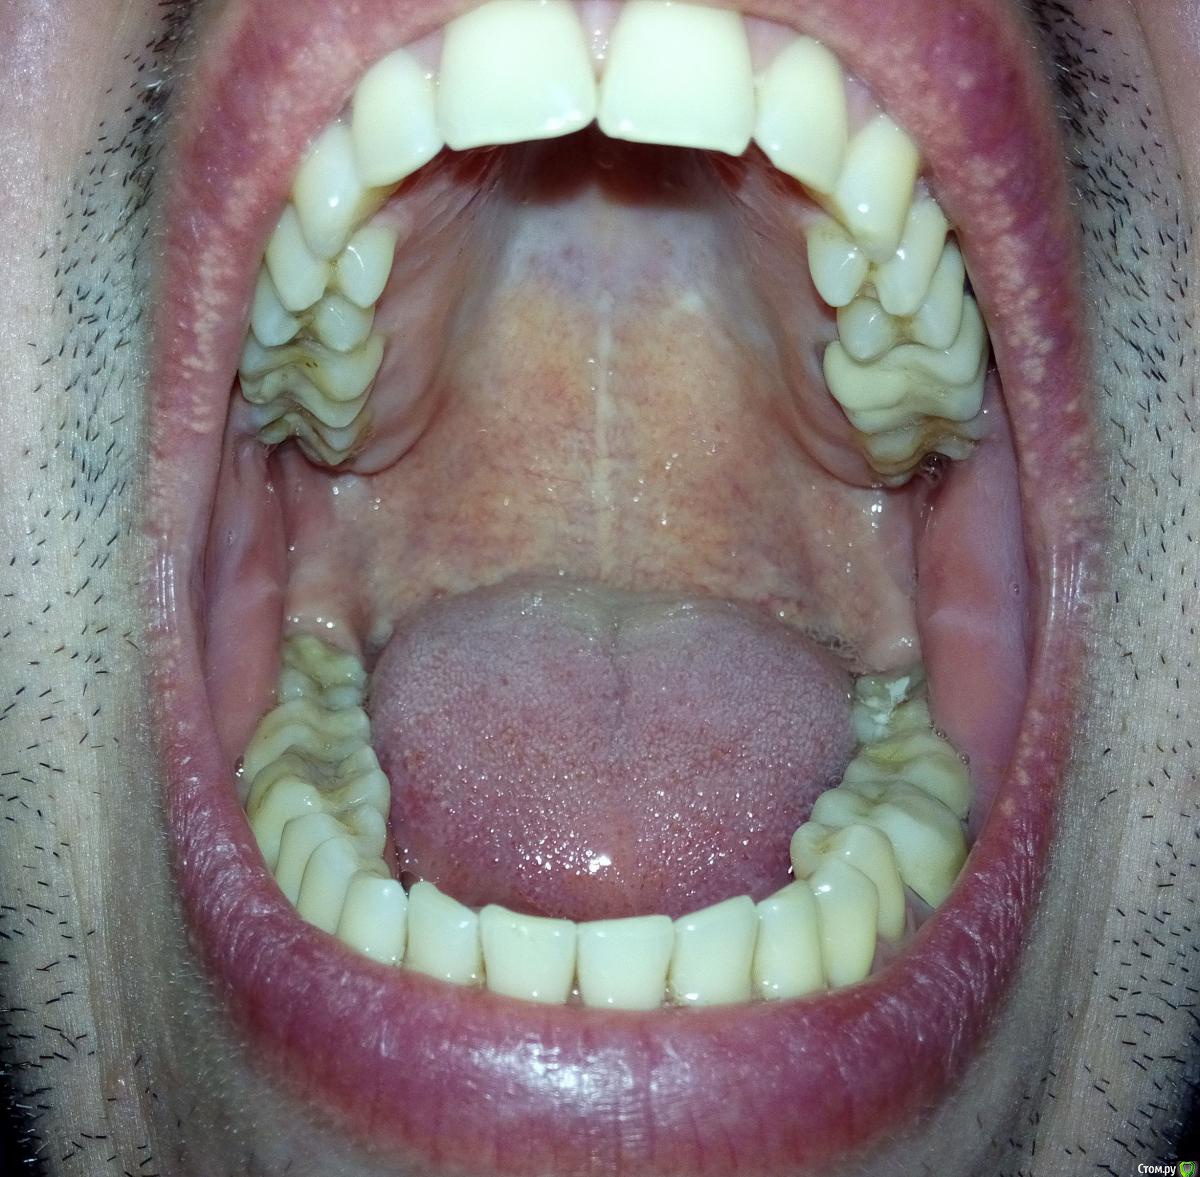

Мне 34 года. В связи с необходимостью перелечивания корней 36 и 37 зубов пришлось заменить металлокерамическую коронку. Однако, она мне не подошла: через несколько дней при смыкании нижняя челюсть начала какбы съезжать впред и влево, начали соприкасаться (ранее такого не было) передние левые зубы. Доктор объяснил это занижнием коронки в области 36 зуба. Сделали новую коронку, которую я носил неделю, но она мне тоже была неудобна (как бы завышала). Ее опять изменили, немного занизили. В результате почти месяц, ношения разных вариантов и в итоге:

* Ни с одним вариантом мне не было удобно. Сейчас не могу сомкнуть зубы, чтоб было удобно сразу и справа и слева как до лечения.

* Дней 14 назад появились боли в жевательных мышцах с обоих сторон. Сейчас болей нет (наверное, благодаря упражнениям описанным ниже), но в внчс справа появились неприятные ощущения и пощелкивания, а слева (где стоит коронка) - похрустывания. Основной дискомфорт в внчс противовположном коронке.

* раньше, со старыми коронками, жевать на эту сторону (где короник) было не совсем удобно. Сейчас, вроде бы, удобнее (субъективно).

* Безболезненно широко открывается рот. Но (!) траектория открытия делает небольшой изгиб отклонение вправо (противовположно коронке и в сторону проблемного сустава). Этот сдвиг происходит при зазоре зазоре 1 см между зубами. Ранее за этим не следил.

-судя по бугристости на углах нижней челюсти и фасеткам стираемости  на многих зубах , Вы- бруксист! и еще тот!)  отсюда и симптоматика, и боли в мышцах.

>>-судя по бугристости на углах нижней челюсти и фасеткам стираемости  на многих >>зубах , Вы- бруксист! и еще тот!)  отсюда и симптоматика, и боли в мышцах.

Дело в том, что жена (человек спящий со мной бок о бок более 10 лет) ни разу не отмечала скрежет во сне. По утрам никогда не болели мышцы. У меня обычно другая проблема -  могу спать с полуоткрытоым ртом так, что (простите за подробность) вытекают слюни и мокнет подушка :-)

Так же могу отметить, что форма старых 36 и 37 металлокерамичких коронок и старых зубов была плоскими (почти ровная площадка), стоматологи это свзязывали с тем, что зубы антагонисты соприкасались бугор-бугор, а не бугор-впадина. Самое инетерсное, что сейчас мне сделали бугры на коронке, которые попадают в впадины, но этот доцент, не зная какими были ранее зубы и коронки, констатировала, что ранее они были плоскими. Может стОит вернуться к старым формам? :wacko: